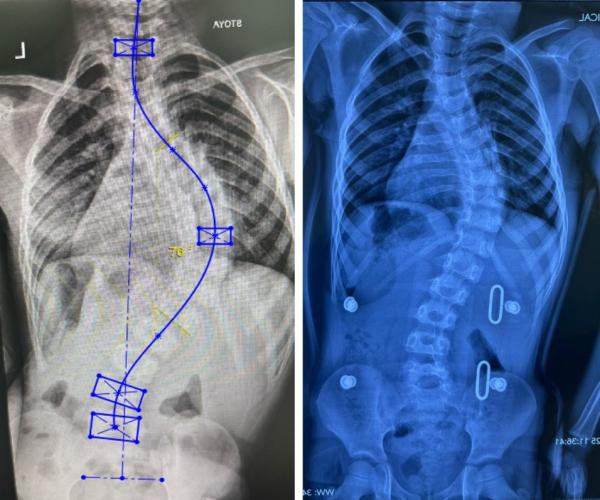

С докладом на тему «Использование 3D-технологий в медицине» выступил врач Ортопедического центра города Алматы Антон Золотухин. По его словам, в их центре такие методы давно внедрены и уже дали результаты — в частности, при лечении идиопатического сколиоза, деформаций черепа у детей до 1,5 лет, а также воронкообразной и килевидной деформаций грудной клетки.

- изготовление корсета Шено при идиопатическом сколиозе,

- хирургическое планирование